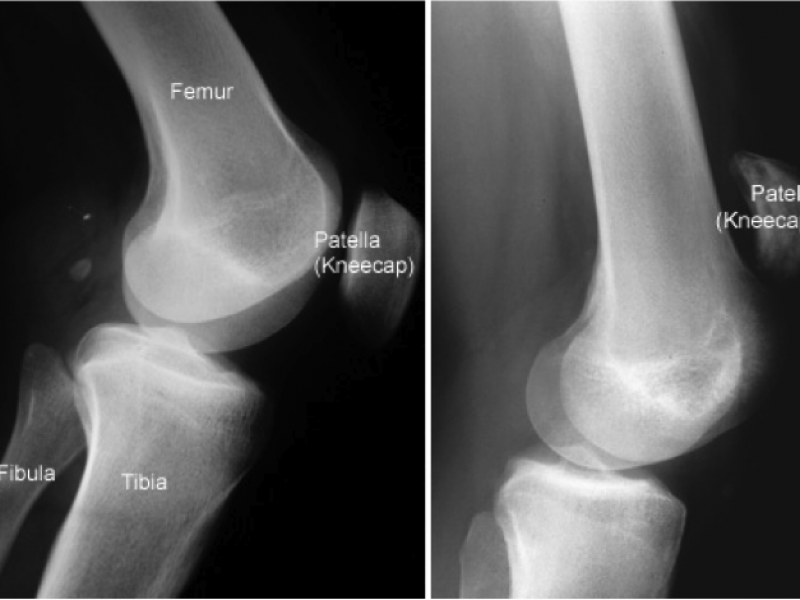

Orthopedic Injuries Around the NFL: Dez Bryant 's Tibial Plateau Fracture

In Week 3 of this NFL season, Dallas Cowboys wide receiver